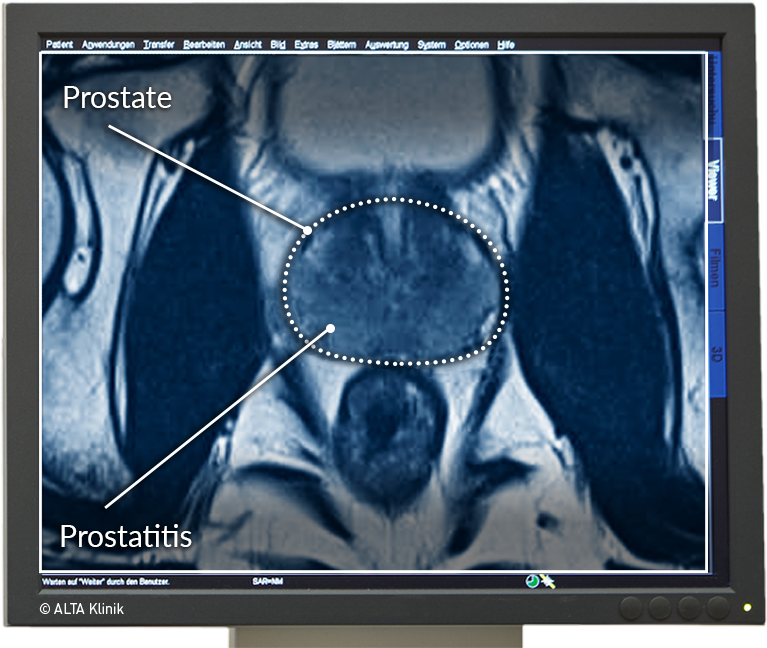

Prostatitis Symptome Anzeichen Behandlung Alta Klinik